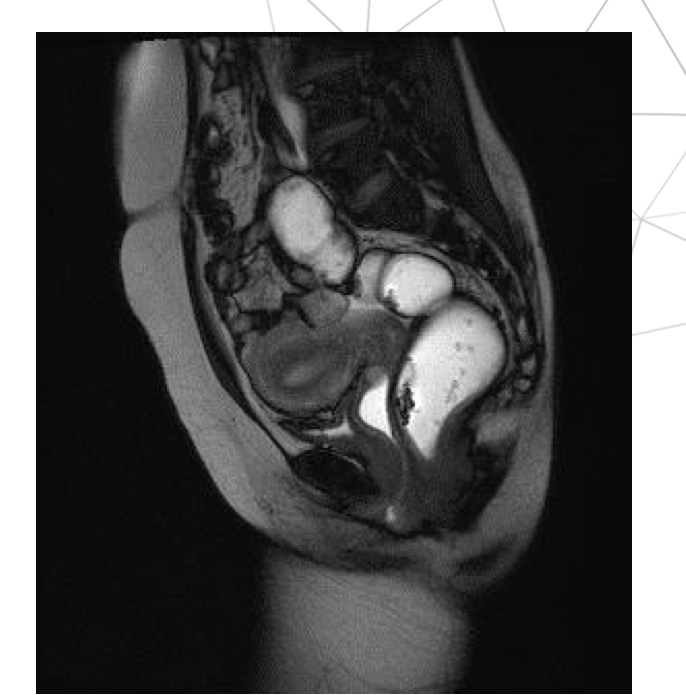

T2w sag, thì nghỉ

Thì nghỉ, T2w ax

T2 cor, thì nghỉ